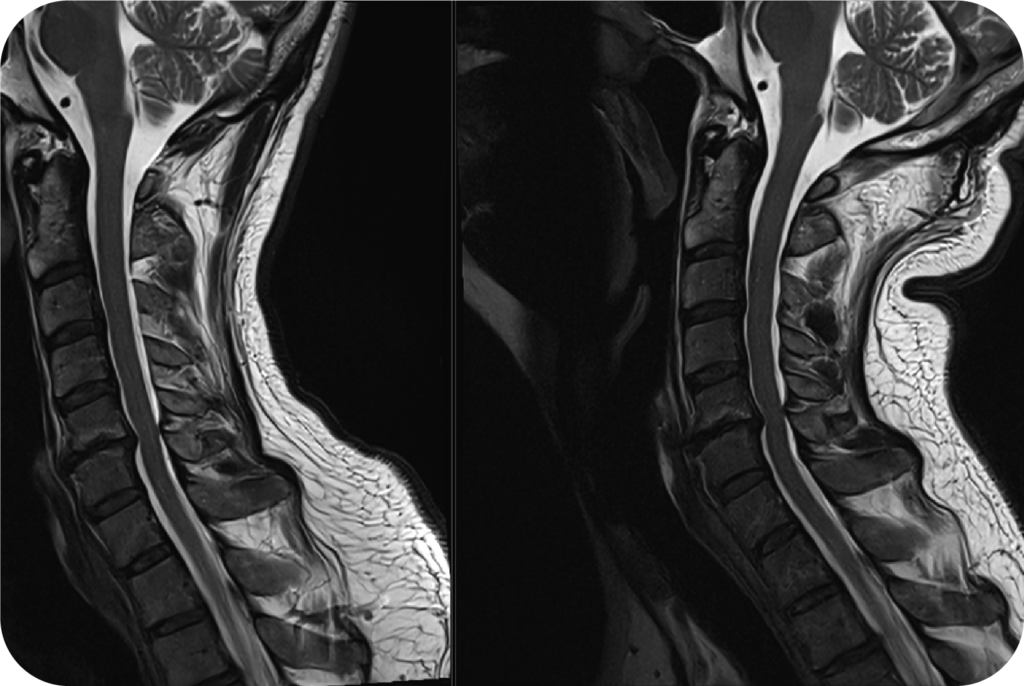

Advanced Imaging Review & Coordination

Objective review of digital X-ray findings and coordination of MRI or specialized MRI when clinically indicated to clarify injuries and the true source of symptoms.

Why Spinal Instability Goes Missed Without Proper Imaging

Why Spinal Instability Goes Missed Without Proper Imaging Spinal instability is one of the most commonly missed causes of chronic pain, especially in patients who have been injured in a…